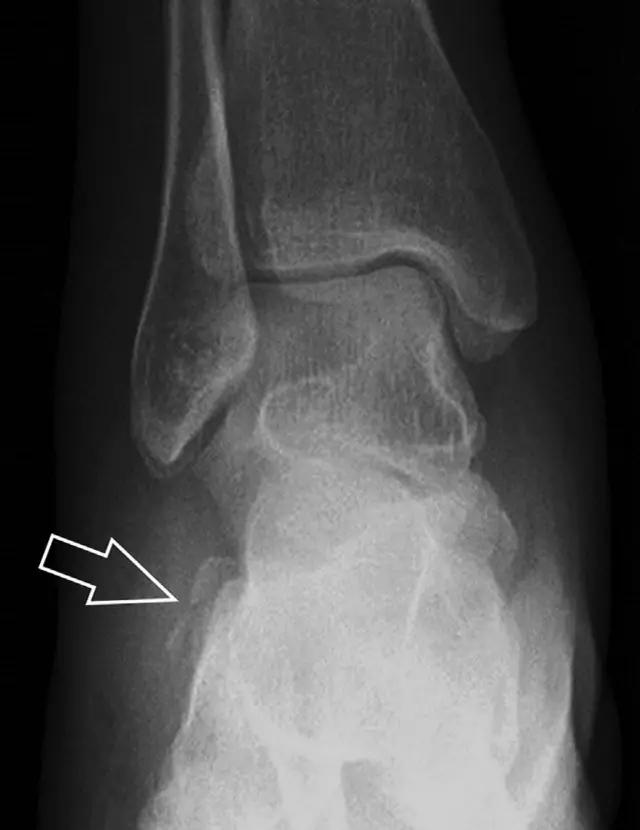

21趾短伸肌跟骨撕脱性骨折另一种重要的跟骨撕脱性骨折,于足内翻时发生在趾短伸肌的起点处。观察来自跟骨背外侧的、不同大小的骨折块,前后位 X 片最适合不过了(图 7)。

图 7 溜冰受伤的患者,趾短伸肌跟骨撕脱性骨折。正位片示 2 个骨折块(箭头)来源于跟骨前外侧、趾短伸肌的起点处。踝关节外侧远端是否存在软组织水肿是一个重点观察点